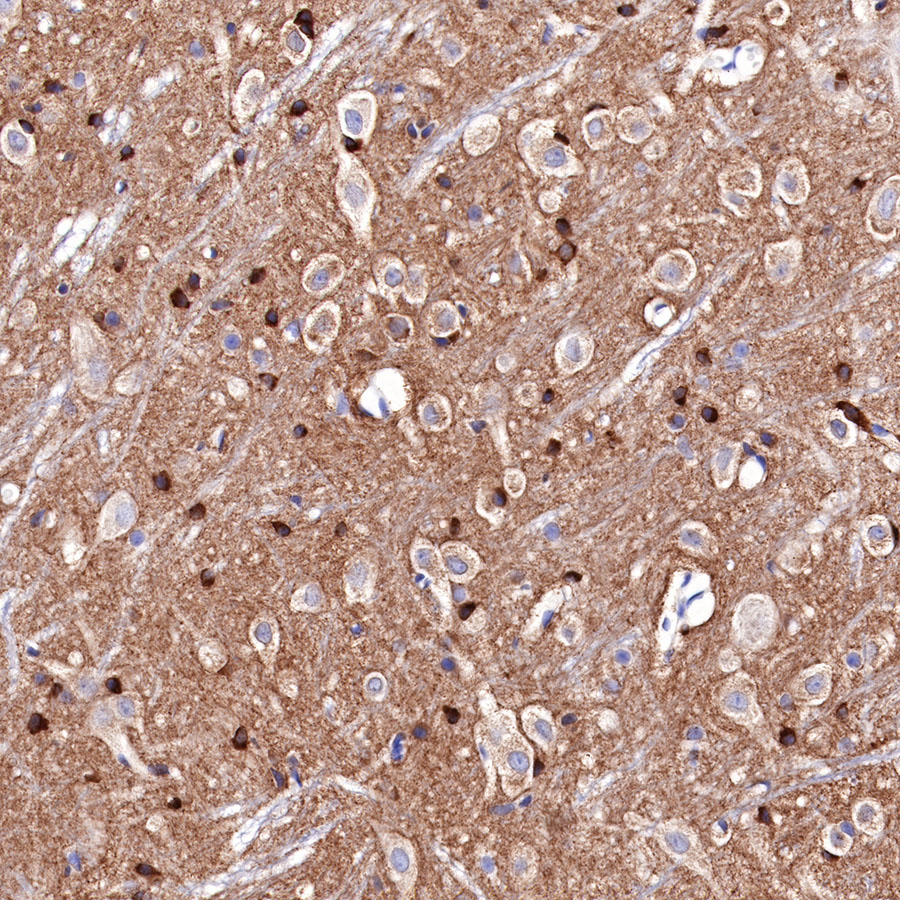

IHC shows positive staining in paraffin-embedded rat cerebral cortex. Anti-Tau antibody was used at 1/2000 dilution, followed by a HRP Polymer for Mouse & Rabbit IgG (ready to use). Counterstained with hematoxylin. Heat mediated antigen retrieval with Tris/EDTA buffer pH9.0 was performed before commencing with IHC staining protocol.